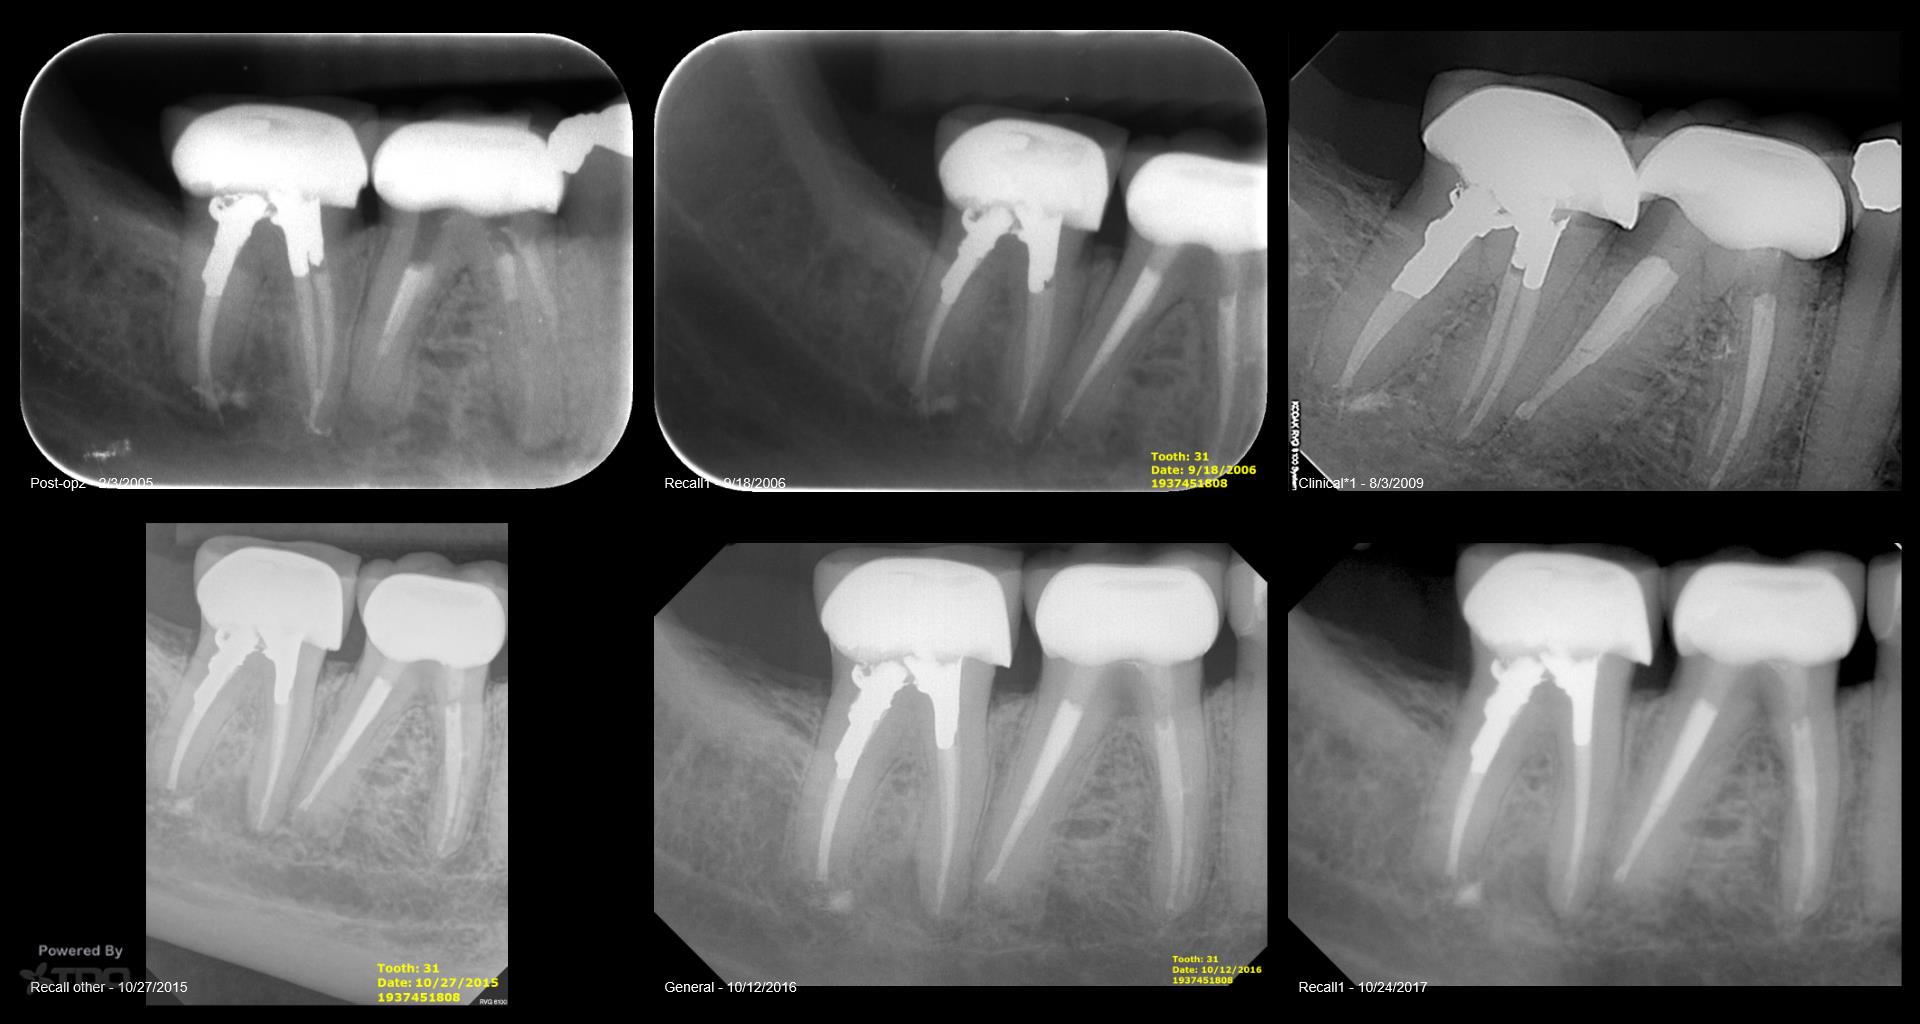

Very compliant patient—always made his recalls. Tooth has been asymptomatic for 15 years…and the periapical area had cleared—-now tender to biting and patient has an ache….No evidence of any occlusal issues. Will start the retreatment…again. Ugh….. gbc